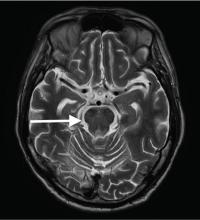

Although CT may underestimate osmotic demyelination syndrome, the typical radiologic findings on brain MRI are hyperintense lesions in the central pons or associated extrapontine structures on T2-weighted and fluid-attenuated inversion recovery sequences.4

Our patient’s clinical course and high hemoglobin A1c suggested prolonged hyperglycemia and high serum osmolality before his admission. After his admission, aggressive hydration and insulin therapy corrected the hyperglycemia and serum osmolality too rapidly for his brain cells to adjust to the change. It was reasonable to suspect a hyperosmolar hyperglycemic state as one of the main causes of his mental status change and ataxia. This, along with lack of improvement in his impaired metal status and new-onset ataxia despite treatment, led to suspicion of osmotic demyelination syndrome. His diminished bilateral knee-jerk and ankle-jerk responses more likely represented diabetic neuropathy rather than osmotic demyelination syndrome.

Osmotic demyelination syndrome has seldom been reported as a complication of hyperosmolar hyperglycemia.6–13 And extrapontine myelinolysis with hyperosmolar hyperglycemia is extremely rare, with only 2 reports to date to the best of our knowledge.6,10